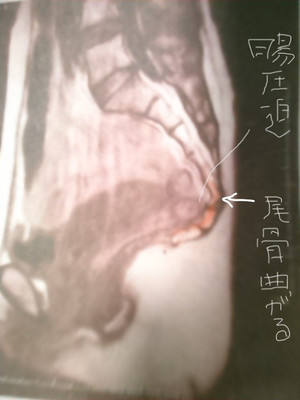

尾骨新鮮骨折は尾骨整復術で後遺症なく予後100良好です。

後遺症とは尾骨痛が骨折治癒期間が過ぎても痛い、自律神経が乱れた、腰痛がおきた、坐骨神経痛がおきた、首痛がおきた、便秘になった、既存症状が重くなったなどがあります。

尾骨骨折は整復術を受けてから約1か月で痛みがなくなっていき骨折治癒期間は2か月です。

尾骨新鮮骨折とは受傷日から3日です。

尾骨整復術はどの期間でも有効です。受傷から1週間、1か月、2か月、1年や10年経ったものまで。

受傷から1週間~2週間たったものでも尾骨整復術で骨折治癒期間と同等の日数で治る可能性があります。